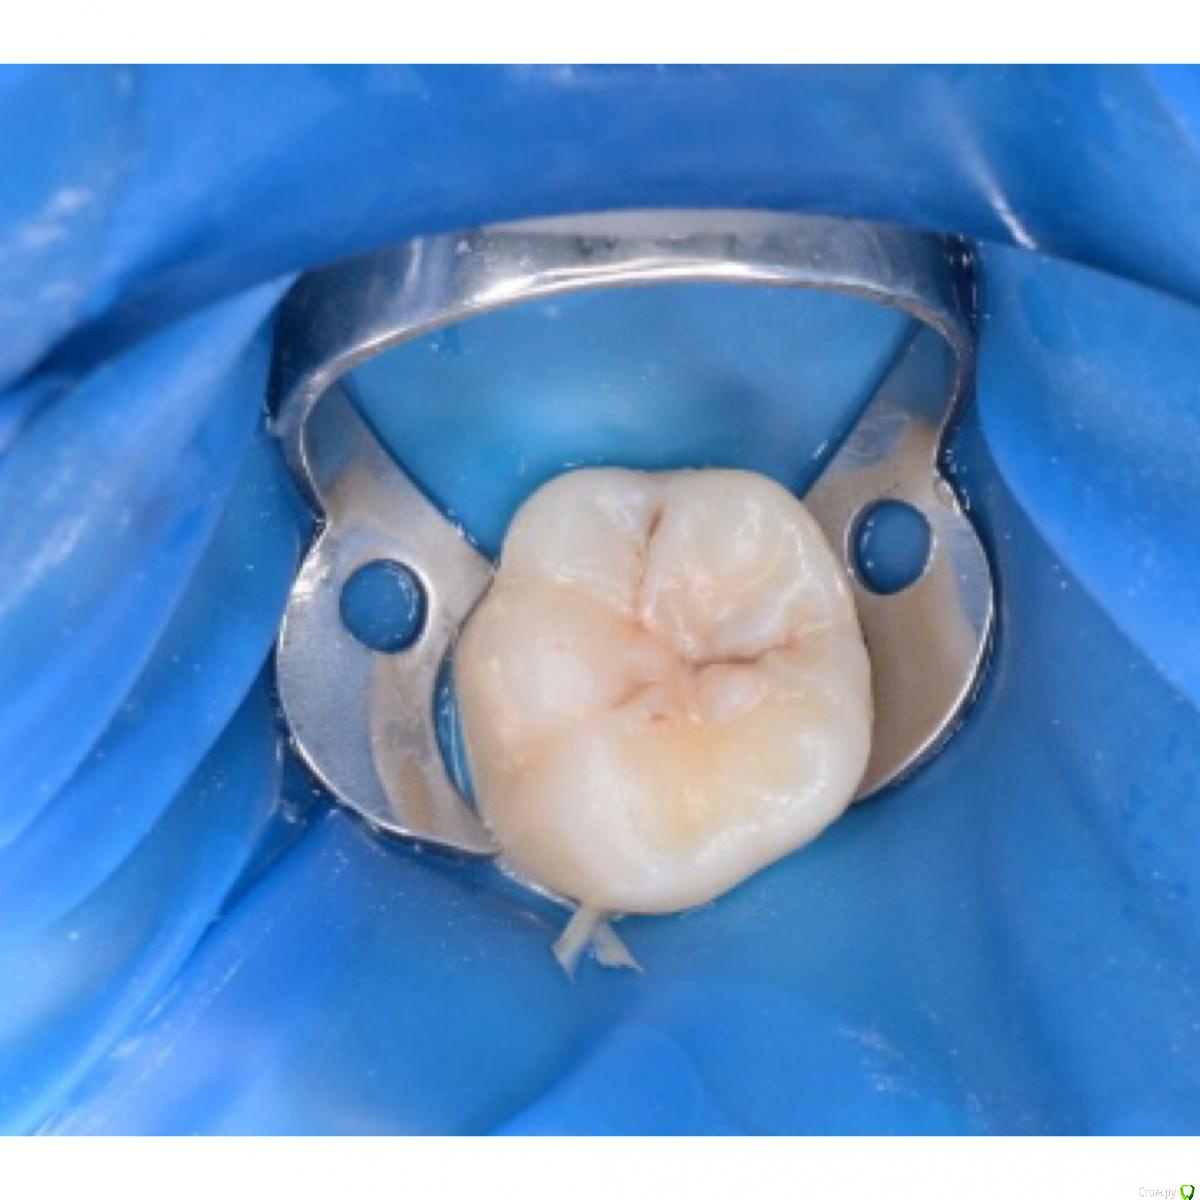

CRAZYDUCK Опубликовано 10 мая, 2018 Автор Поделиться Опубликовано 10 мая, 2018 Кариес 1.6 , ребёнок 11 лет . Коффердам порвала , контакт заполировала . 5 Ссылка на комментарий